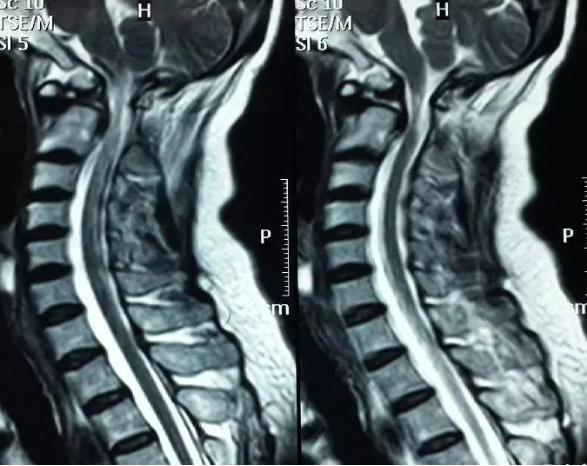

3影像学检查

手术前后伸前屈位X光片寰枢椎脱位为可复性(后伸位脱位复位,前屈位寰齿前间隙(ADl)大于5mm)。寰枢椎CT椎弓根发育良好(大于4mm),磁共振脊髓损伤伴椎管狭窄。

全麻后,显微镜下行颈后路减压+寰枢椎(C1~2)复位椎弓根螺钉钛棒内固定+植骨融合术。术中C臂下行C1~2复位椎弓根置钉。术后三个月复查见椎管减压后脊髓位置良好,寰枢椎脱位复位,局部可见骨融合。患者自述四肢麻木无力感明显好转。